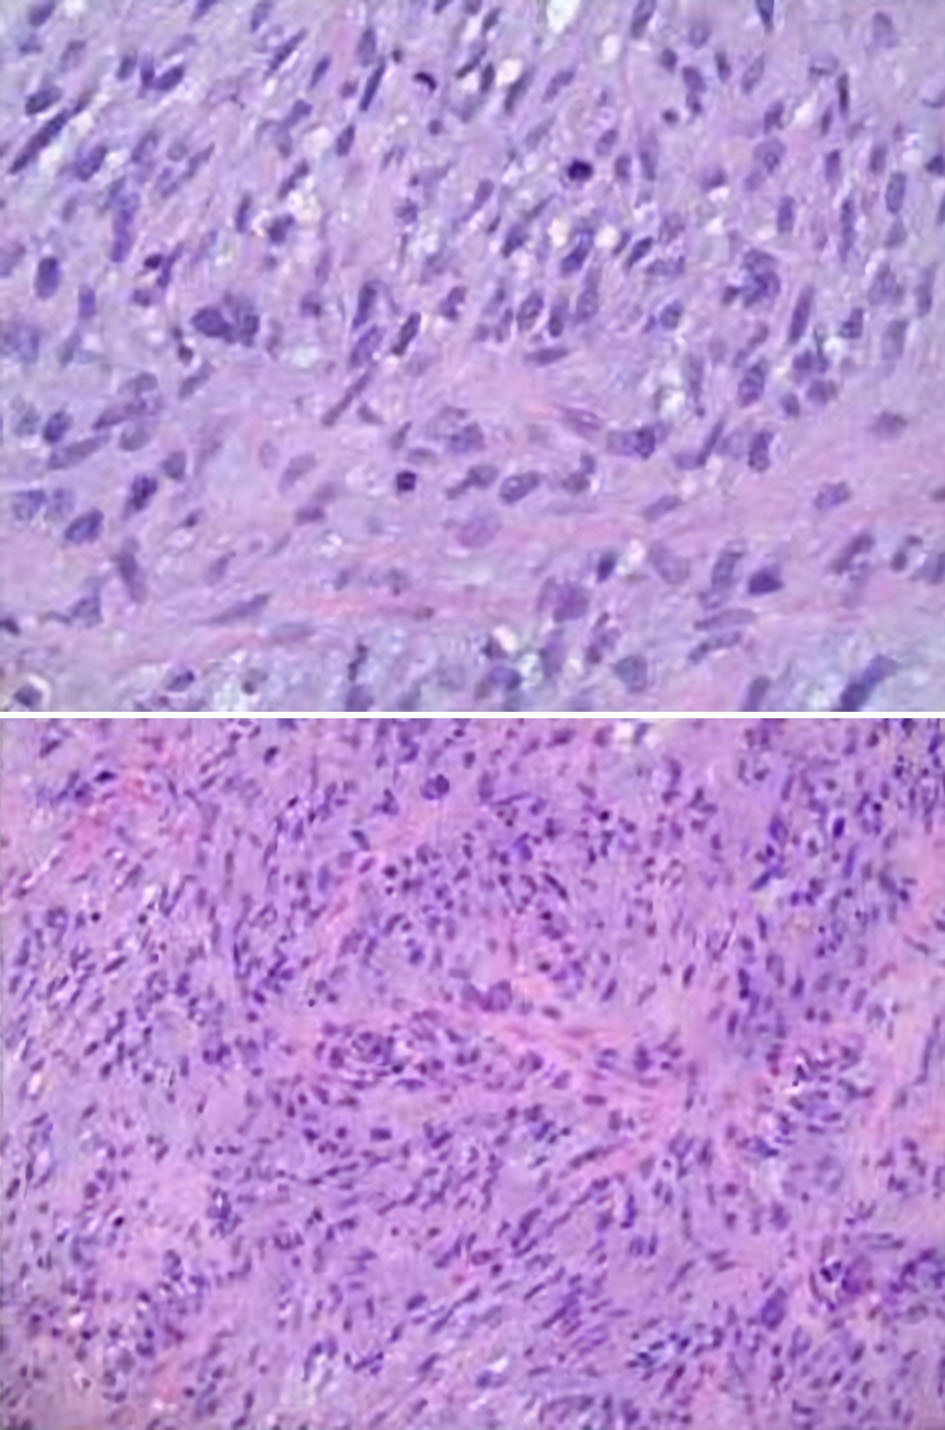

Figure 8. Microscopic pathology images demonstrating cardiac undifferentiated pleomorphic sarcoma (UPS), grade 3. The histology displays variable cellularity, with areas of marked pleomorphism, as well as foci of myxoid change and focal necrosis. Mitoses are easily identified in some areas and are scarce in others. These features support the interpretation of an UPS.